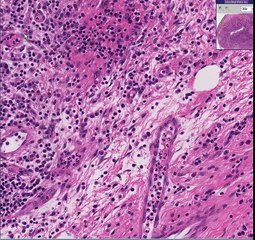

Squamous Cell Skin Cancer explained by Dr Barry Lycka

Squamous cell skin cancer, also known as squamous cell carcinoma – are you at risk, do you have one? If you have sun exposed skin, watch this video from Dr Barry Lycka to discover more.